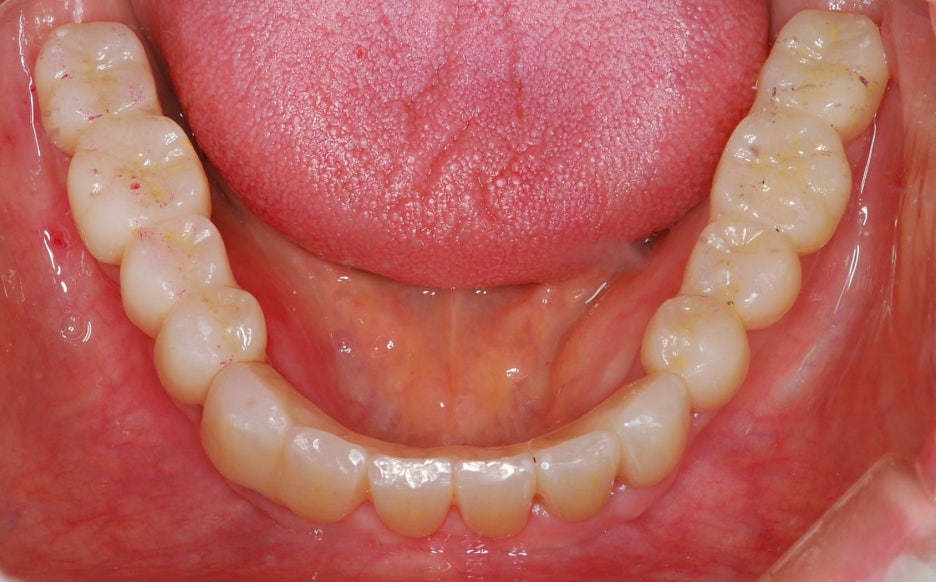

무치악환자를 위한 전악임플란트

전악임플란트 중점 치료

<참고이미지> 무치악 환자의 임플란트 치료 사례 / 환자에 따라 치료결과는 다를 수 있으며 임플란트 주위염 등이 발생할 수 있습니다.

무치악 환자에게 적용시 치아의 기능을 일정수준으로 회복할 수 있는 치료입니다.

20.09.19 경과체크 / 무치악 임플란트 치료 / 환자에 따라 치료결과는 다를 수 있으며 임플란트 주위염 등의 부작용이 발생할 수 있습니다.

기능의 회복은 물론 심미적인 목적도 충족 시킬 수 입니다.

치아의 상태와 잇몸뼈 상태를 고려한 식립

필요한 개수만큼 식립하여 경제적으로 치료 받을 수 있습니다.